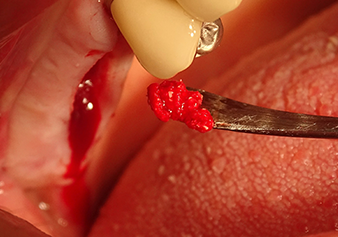

À l'aide d’une rugine, un mélange d’augmentation est soigneusement placé dans la région de l’ostium du sinus maxillaire interne, dans la direction apicale.

Fig.8 : À l'aide d’une rugine, un mélange d’augmentation est soigneusement placé dans la région de l’ostium du sinus maxillaire interne, dans la direction apicale.